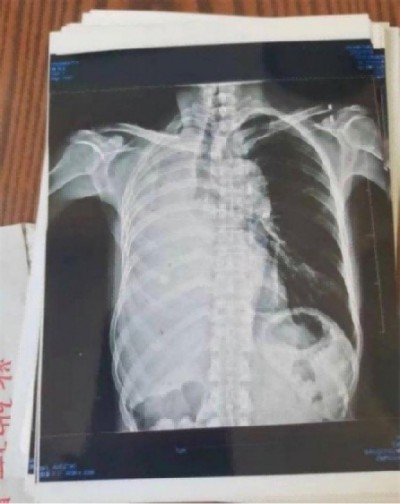

近日,陈海林教授中医治疗成功挽救重症患者的消息引起了广泛关注。据悉,该患者陈香花在经历了西医的多次手术、化疗和放疗之后,身体状况急剧恶化,最终被多家医院拒之门外。在生命即将走到尽头的时候,被好心人送到陈海林中医诊所。更严重的是该患者有多种严重疾病缠身,包括失去右肺、左肺功能仅剩三分之二,并伴有心脏病、贫血、高血压等十多种基础疾病,生命垂危。面对这样一位多种病且复杂的危重患者,陈海林教授秉承救命优先的原则接诊了这位患者,经过仔细的辨证施治,陈教授为患者制定了一套个性化的中医治疗方案,在经过长达七个月的纯中医治疗后,患者竟奇迹般地恢复了健康,重新获得了新生,也创造了中医药治疗重症肺癌的奇迹。

国家医学教授楷模——陈海林教授获国际认可

六年后,当陈教授再次回访了这位患者。走进她的家中见到了这位曾经命悬一线的患者,如今她已恢复了正常的生活。回忆起那段艰难的治疗过程,她感慨万千,对中医的神奇疗效赞不绝口,也感恩陈海林教授给了她第二次生命,在曾经对治疗失去了信心,但是在陈教授的帮助下,我重新找回了生活的希望,也让她对生命充满了感激和珍惜。